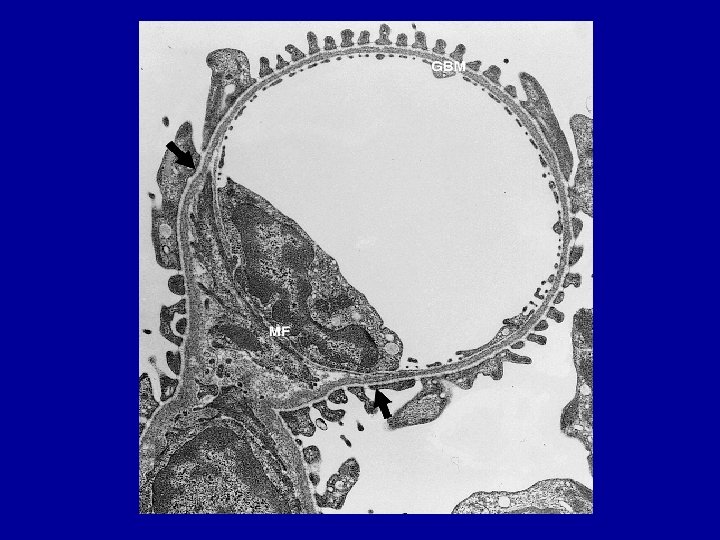

Endotelio di un capillare glomerulare (lamina fenestrata)

PP = Podociti. FF = Foot processes (processi pedicellari)

Membrana Basale Struttura proteica • E’ interposta tra epitelio (podociti) ed endotelio (lamina fenestrata) • E’ formata da tre strati (lamina densa, lamina rara interna e lamina rara esterna) • Ha uno spessore complessivo di 2400 -3400 A° • Ha carica elettronegativa (conferita dai proteoglicani) • Presenta fenestrazioni sul versante endoteliale di 700 -900 A° e pori sul versante epiteliale del diametro di 200 -400 A°

Johnson-Feehally Slits pore Lamina fenestrata